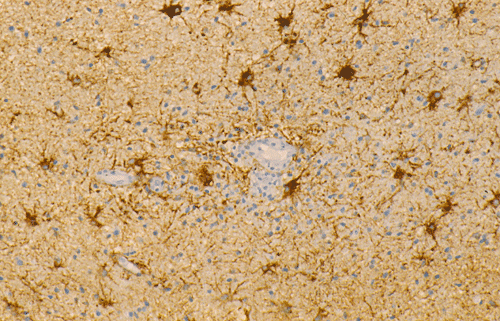

GFAP

CD68

Streotactic biopsy yielded several cores of tissue. On scanning magnification, there are multiple small lymphocytic collections (Ž in Panel C) in the white matter. On higher magnification, these areas contain mostly lymphocytes without atypia. These collections appear to be angiocentric and are often admixed with some foamy macrophages (Panel  D and E). On LFB/PAS stain, multiple small, irregular areas of angiocentric pale staining are present (Panel F and G). On high magnification, these areas are featured by infiltration by foamy macrophages and lymphocytes and myelin loss (Panel  H). On Bielschowsky stain, the axons in these pale areas are largely preserved. Immunohistochemistry on GFAP demonstrates multiple stellate reactive astrocytes (Panel J). The macrophages and lymphocytes are also well demonstrated by immunohistochemistry for CD68 and LCA respectively (Panel  K and L).

The histopathology of inflammatory demyelinating pseudotumors is very similar to that of acute disseminated perivsnous encephalomyelitis or the classic type of ADEM. In essence, there is perivenous chronic inflammatory cell infiltration accompanied by infiltrating, foamy macrophages with an angiocentric distribution. Loss of myelin and relative preservation of axon fibers must be demonstrated before a diagnosis of demyelinating process is made. The loss of myelin can be well demonstrated by special stains for myelin with the Luxol fast blue based stains as one of the most commonly used stains. Relative preservation of axons can be sell demonstrated by silver stains such as Bodian stain, Bielschowsky stain, and also immunohistochemistry for moderate and high molecular weight neurofilament proteins. The pathologic highlights on separating inflammatory demyelinating lesions from mimicking lesions have been well described by Zagzag et al. 8. Other inflammatory lesions, particularly viral infectons, must also be ruled out. Keen observations particularly for nuclear inclusion bodies, immunohistochemistry for specific viral agents, and laboratory studies of the cerebral spinal fluid (CSF) and blood are often helpful. Identification of oligoclonal bands on electrophoresis of CSF is a strong suggesting of a demyelinating process.